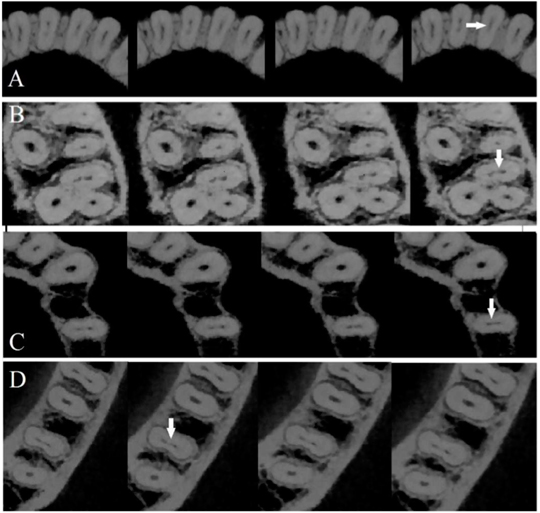

Los escaneos de dientes con istmos completos se reevaluaron en planos axial, sagital y coronal con un grosor de 0,1 mm. Se informó la presencia y ausencia de istmo completo en cada diente. El conducto radicular se dividió en 3 partes iguales (tercio cervical, medio y apical), así mismo el istmo se clasificaron con respecto a los puntos de inicio y final. Los hallazgos se clasificaron en 6 categorías con respecto a los puntos de inicio y fin del istmo: 1) el comienzo y el final en el tercio cervical; 2) el comienzo en el tercio cervical y el final en el tercio medio; 3) el comienzo en el tercio cervical y el final en el tercio apical; 4) el comienzo y el final en el tercio medio; 5) el comienzo en el tercio medio y el final en el tercio apical y 5) el comienzo y el final en el tercio apical. (Figura 1)

Obteniendo como resultado que la prevalencia de istmo completo en dientes permanentes fue del 8,6%, y la mayor prevalencia se informó en las raíces mesiales de los primeros molares mandibulares. En el maxilar, la mayor prevalencia de istmo completo se encontró en las raíces mesiovestibulares de los primeros molares superiores, mientras que en los caninos y los incisivos centrales no se detectaron istmos. En la mandíbula, la menor prevalencia de istmo se encontró en segundos premolares. En los molares maxilares, el istmo que comienza y termina en el tercio medio de la raíz tiene la mayor prevalencia.

Por otro lado, los istmos en los molares mandibulares, desde el tercio apical o medio de la raíz que comienza hasta el final del tercio apical, tuvo la mayor prevalencia.